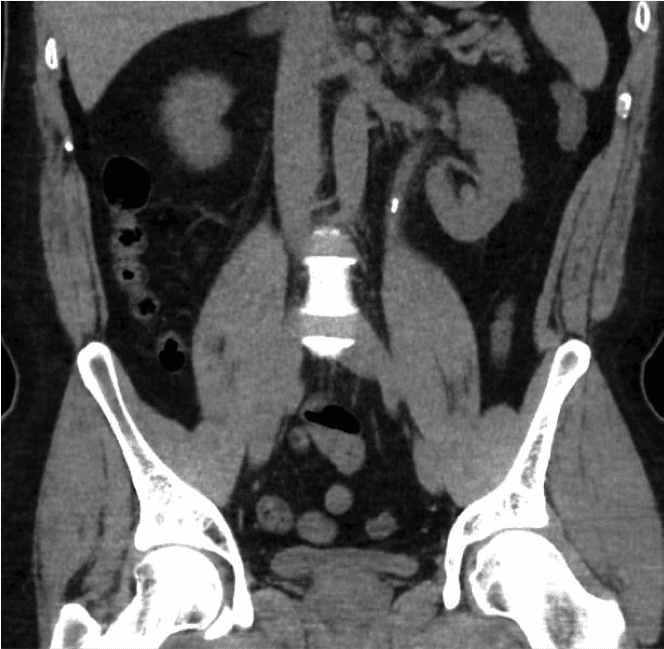

Inizialmente verrà eseguito un test con stick urinario per verificare la presenza di sangue nelle urine ed escludere un'infezione urinaria. Vengono eseguiti esami del sangue per la funzionalità renale e la calcemia. Il test diagnostico definitivo per i calcoli è una TAC semplice dell'addome (TC Rene Uretere Vescica o TC KUB). Questa scansione mostrerà le dimensioni e la posizione dei calcoli, aiutando a pianificare il trattamento.